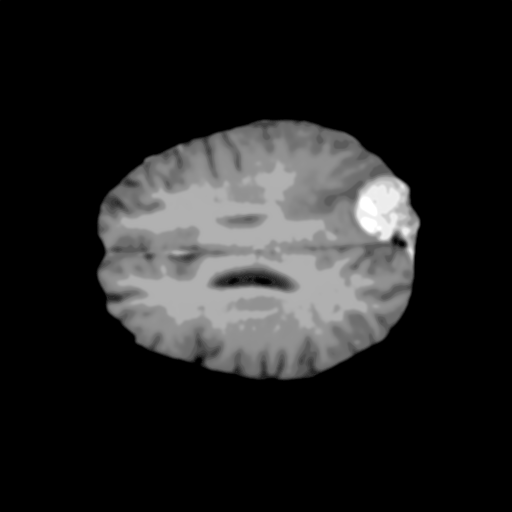

Extensive experiments have been performed in the current setup, and experimental outcomes are reported with the demonstration of numerical and statistical analyses using the proposed QFS-Net, QIS-Net [39], convolutional U-Net [18] and Residual U-Net (URes-Net) architectures [20]. The human expert segmented skull-tripped contrast enhanced DSC brain MR input image slices of size and ROIs are provided in Figure 5 as samples. The demonstration of QFS-Net segmented images followed by the essential post-processed outcome on the slice no. for class level with four distinct activation schemes () are shown in Figure 6. It is evident from the experimental data provided in Table LABEL:tab1 that the proposed QFS-Net performs optimally for the -connected quantum fuzzy pixel information heterogeneity assisted activation () with and gray scale set in comparison with other thresholding schemes and gray scale sets under the four evaluation parameters () [44]. The segmented tumors obtained using the proposed self-supervised procedure under class transition levels with four different thresholding schemes , , and are demonstrated in Figures 7- 8 for the class boundary sets and [39], respectively. The segmented images using the remaining two class boundary sets ( and ) [39] are provided in the supplementary materials section. The segmented ROIs describing the whole tumor region after the masking procedure using QIS-Net, U-Net and URes-Net are also reported in Figure 9.